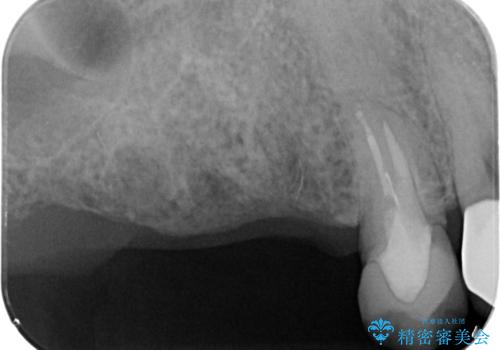

- 歯が抜けてしまい、噛めなくなった右側奥歯の治療を希望され来院されました。

しっかりと咬合機能の回復をするためにインプラント治療を選択されました。